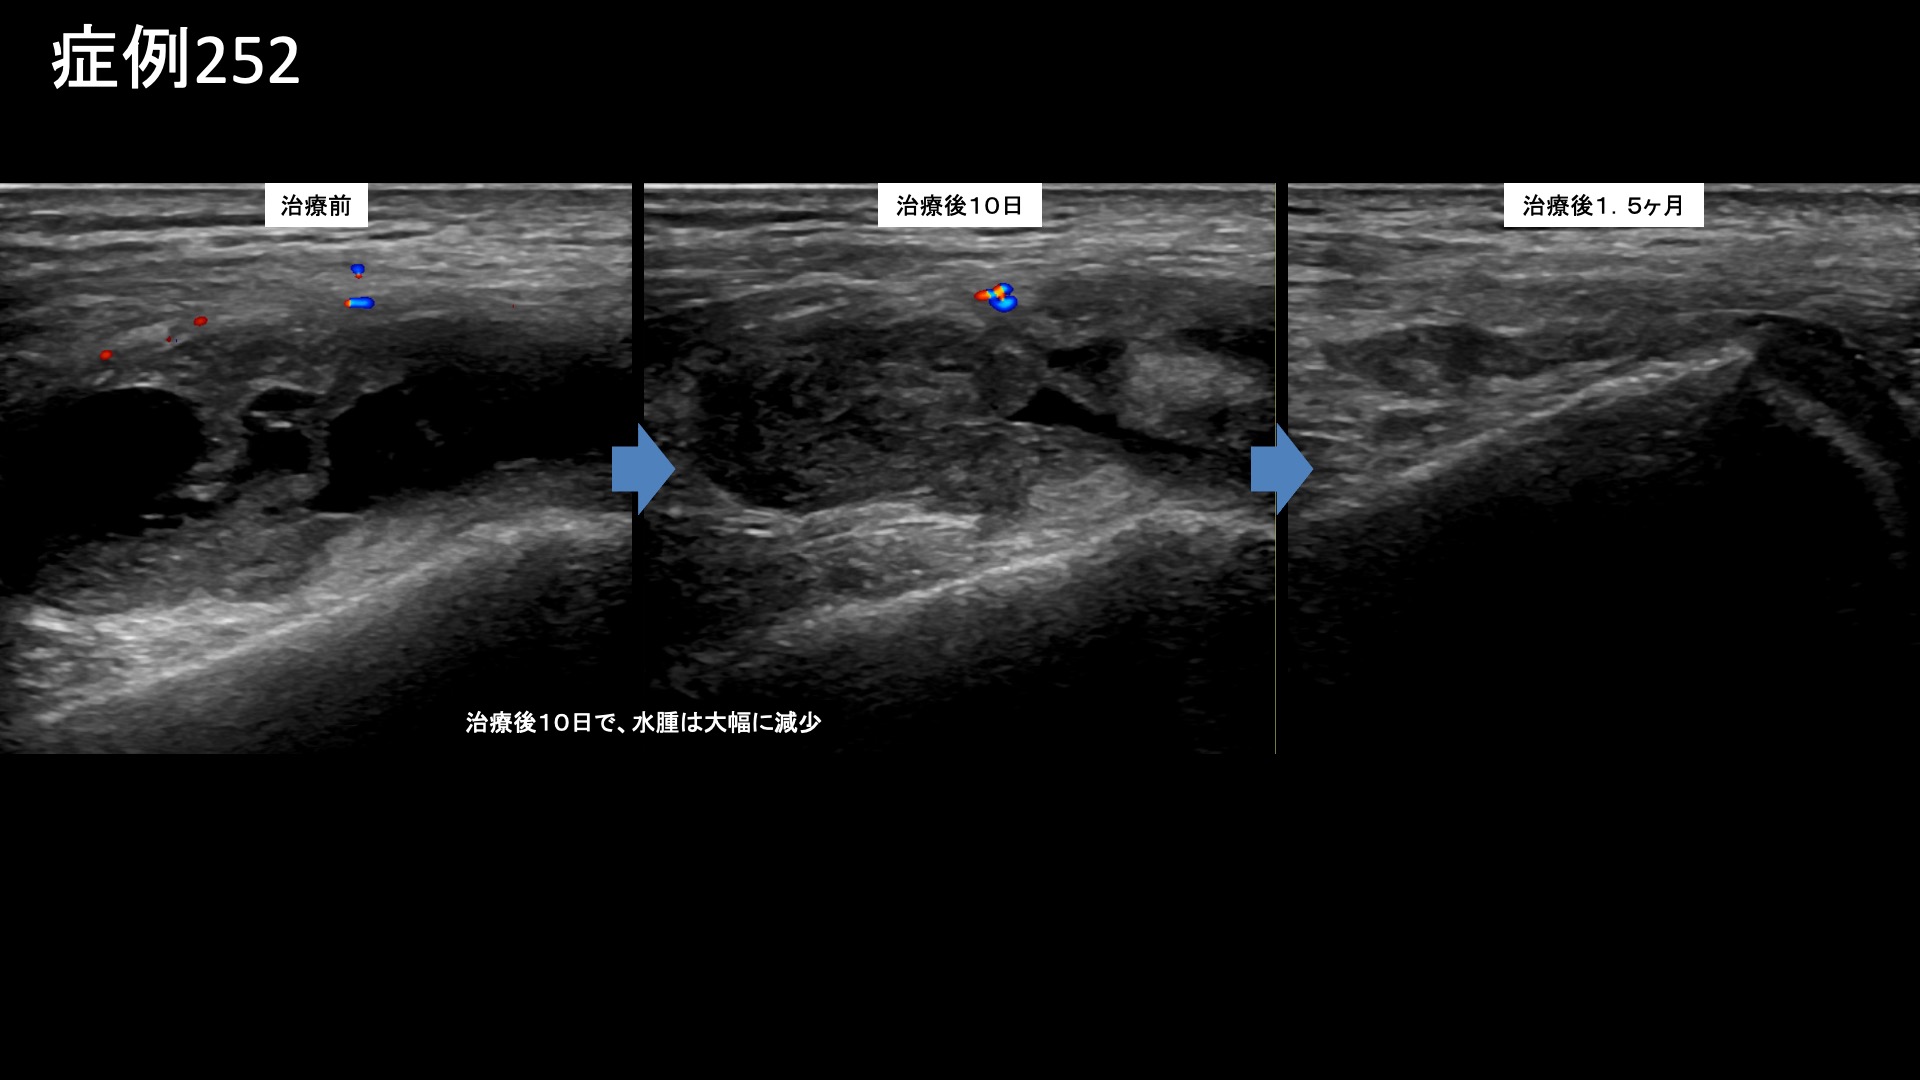

膝:変形性膝関節症など 【70代:男性】急激に悪化した膝の痛みで歩けなくなり夜も寝られず水も溜まる・・ネフローゼ症候群を合併した変形性膝関節症の実例(変形性膝関節症、ネフローゼ症候群) 2025.12.01 鴨井院長による動画解説 受診までの経過 それまで痛めたことはなかったのですが、3ヶ月前から急に右膝が痛み始めました。整形外科を受診し、水を抜いてもらいヒアルロン酸注射を受けていましたが改善しませんでした。松葉杖を使うほどの痛みにもなり、安静時にも痛むようになりました。ついには夜間に痛みで目が覚めるほどになりました。鎮痛薬も効かない一方で、外科手術の適応ではないと言われ思い悩んでいたところ、当院の治療を知り受診されました。 既往疾患;ネフローゼ症候群 診察時の所見 杖歩行にて入室されました。レントゲンでは中等度以上(KL分類3相当)の関節変形を認めました。エコー検査では、膝蓋上嚢に中等度以上の水腫を認め、その周囲や滑膜組織には炎症によるモヤモヤ血管を反映した異常血流信号が豊富に認められました。変形性膝関節症の診断ですが、病状は重症でした。基礎疾患としてのネフローゼ症候群が少なからず影響を与え、炎症が助長されていることが示唆されました。非常に強い炎症が関与していることから良い治療適応と判断し、モヤモヤ血管(病的新生血管)に対する運動器カテーテル治療(微細動脈塞栓術)を受けていただきました。 治療の所見 血管造影を行うと、外側上膝動脈、下行膝動脈などでモヤモヤ血管が濃染像として描出されました。治療後は画像上速やかに消失しました。その他複数箇所の治療を行い終了しました。 尚、強い炎症を反映して、治療時の再現痛は強めでした。 *再現痛とは、薬液投与時に普段の痛みが一定程度再現される現象です。責任血管の同定のための参考とします。 治療後の経過 治療翌日から改善しました。治療後3週間では、ほとんどの痛みが無くなりました。肩関節の可動域も完全に回復し、バンザイもできるようになりました。半年間苦しんでいた痛みのあまりの回復ぶりに、『最初からここに来ればよかった』と話されるほどでした。エコーで確認すると、まだ石灰沈着については大きな変化はありませんでしたが、今後吸収されていくことも期待できます。非常に経過良好であったことから、終診となりました。石灰沈着性腱板炎は強い炎症を伴っていることが多く、その苦痛も五十肩以上になることが少なくありません。カテーテル治療は強い炎症にこそ、強い効果を発揮します。実際に、本症例では非常に早期から快復しました。罹病期間が長くなければ、石灰も吸収されて無くなります。 非常に良い適応疾患の一つですので、お悩みの方はぜひご検討いただくと良いと思います。 治療前画像:損傷を受ける、あるいは繰り返しのストレスにより発生した異常な新生血管 治療後画像:カテーテルを用いて塞栓物質を血管内に投与し新生血管を塞いだ状態 治療費用:治療する部位によって費用が異なりますのでこちらをご参照ください。 主なリスク・副作用等:針を刺した場所が出血により腫れや痛みを生じたり、感染したりすることがあります(穿刺部合併症)。造影剤によるアレルギー(皮膚のかゆみ・赤み・息苦しくなるなどの症状)が出ることがあります。 変形性膝関節症の詳細 【50代:男性】最初からここに来ればよかった・・ステロイド注射無効で半年間苦しんだ石灰沈着性腱板炎による肩の痛み(石灰沈着性腱板炎、肩関節周囲炎) 前の記事 【40代:男性】新型コロナウイルスワクチン接種後、3年に亘り続いたしつこい肩の痛み。石灰沈着性腱板炎後遺症に対するモヤモヤ血管治療(石灰沈着性腱板炎後遺症、SIRVA、新型コロナウイルスワクチン接種) 次の記事